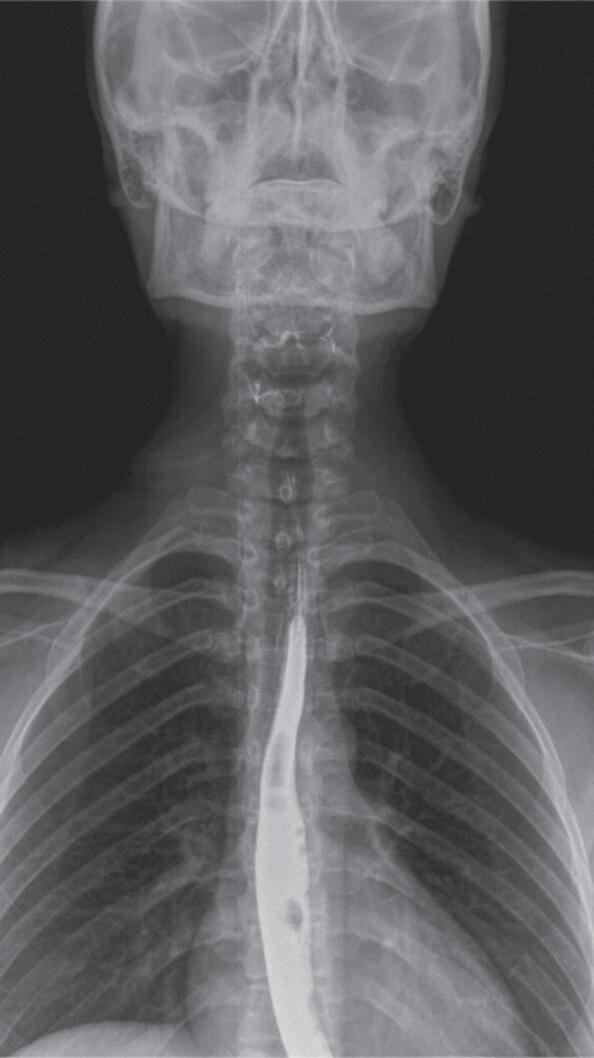

Fig. 1-1. Montagem de duas imagens radiográficas em visão anteroposterior demonstrando o percurso da deglutição desde a cavidade oral até o estômago (a) no adulto e (b) no bebê.

Fig. 1-2. Demonstração das estruturas envolvidas no processo da deglutição nas visões (a) lateral e (b) anteroposterior na imagem radiográfica.